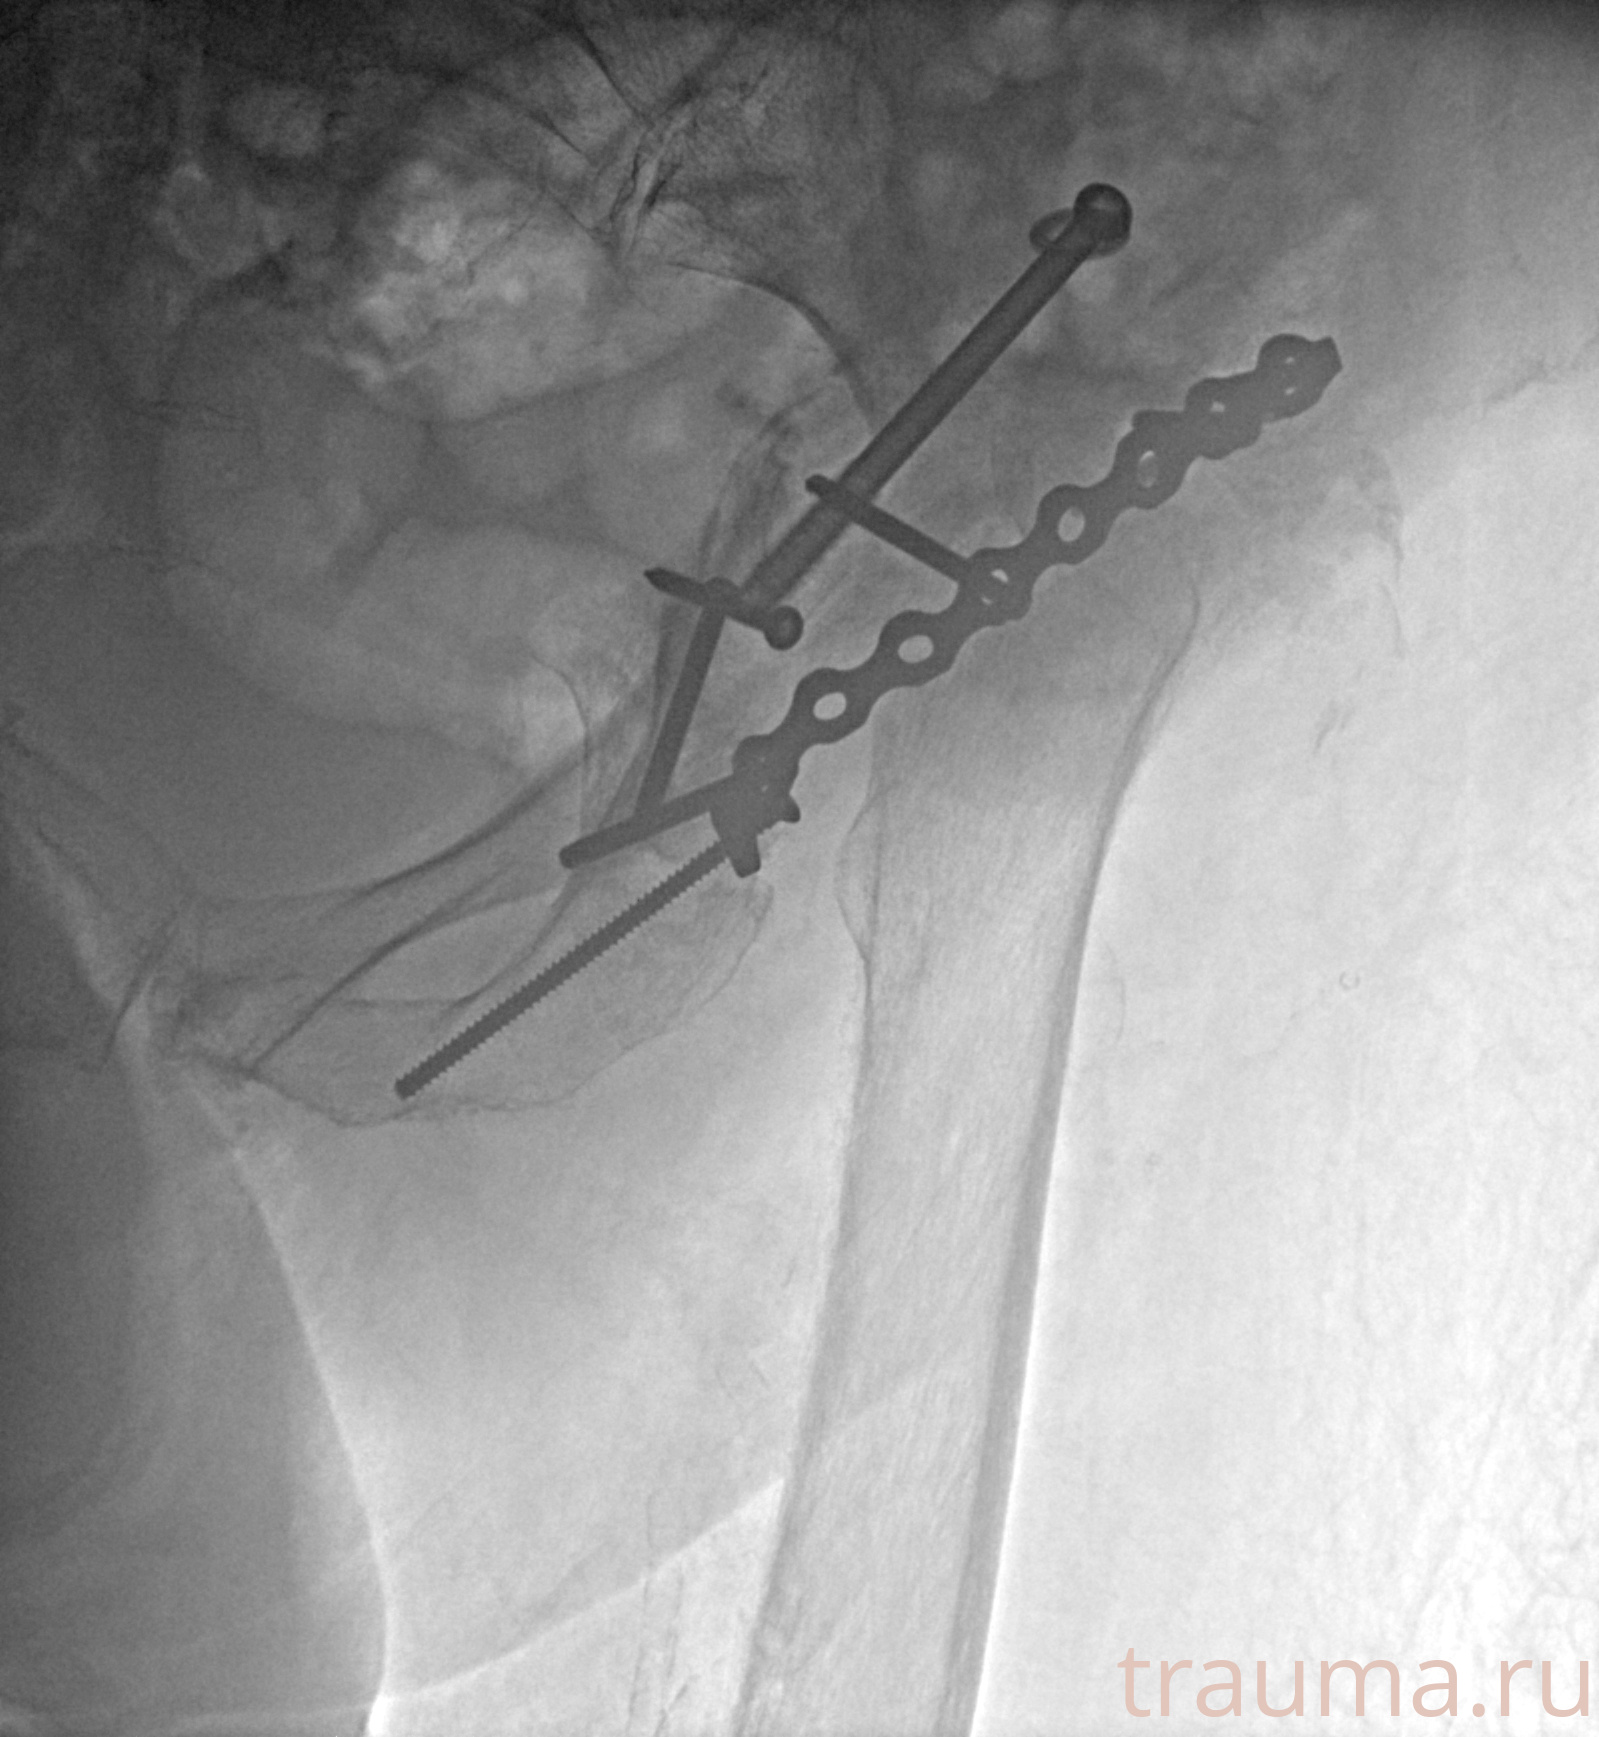

Рентгенограммы

Рентген на дому: по вашему адресу приезжает врач-рентгенолог, травматолог-ортопед с мобильным рентгеновским аппаратом, проводит диагностику травмы или заболевания, делает необходимые рентгенограммы, дает рекомендации по дальнейшему лечению. Получить качественные снимки в домашних условиях возможно благодаря уникальной методике, разработанной МосРентген Центром для института  Склифосовского